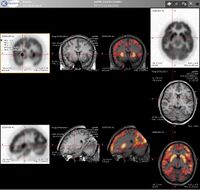

التصوير المقطعي بالإصدار البوزيتروني إنگليزية: Positron Emission Tomography أو PET تقنية تصوير في الطب النووي تسفر عن معطيات وصور ثلاثية الأبعاد لمجرى مختلف العمليات الوظيفية في الجسم. ويعمل الجهاز المصوّر على أساس اكتشاف أزواج من أشعة غاما المنبثفة بشكل غير مباشر عن نظير مشع مصدر للبوزيترونات (قائفة مشعة)، والتي يتم إدخالها إلى الجسم بعد أن ترتبط بجزيء فعال حيويًا). من ثم، يتم استبناء الصورة ثلاثية الأبعاد من الإسقاطات بشكل محوسب. في الآونة الأخيرة، أصبحت تستعمل أجهزة تسهل الاستبناء بواسطة استعمال التصوير الطبقي المحوسب بواسطة الأشعة السينية (أشعة إكس) والذي يتم إجراءه في نفس جهاز التصوير بالإصدار البوزيتروني وفي نفس الوقت.

لإجراء التصوير، يتم حقن الشخص الخاضع للتصوير بقائفة التي هي عبارة عن نظير مشع ذي عمر قصير، وعادة ما تحقن المادة إلى الدورة الدموية. وعادة ما تحقن القائفة بعد أن يتم دمجها في جزيئات فعالة حيويًا. بعد فترة انتظار، يرتفع خلالها تركيز القائفة في الأنسجة المرغوب تصويرها، يتم وضع الشخص في جهاز التصوير التفرسي (الماسح). ويعرف الجزيء الأكثر استعمالاً في تصوير الإصدار البوزيتروني باسم فلوريد الجلوكوز منقوص الأكسجين (FDG)، وهو من السكريات، ويكون زمن الانتظار بعد الحقن لدى استعماله ساعة واحدة تقريبًا. في خلال عملية التصوير يتم تسجيل تركيز القائفة في النسيج، في حين تتحلل القائفة بشكل طبيعي وفق عمر النصف خاصتها.

وفق الإحصائيات الملتقطة من تزامن اصطدام أزواج فوتونات بالمفراس، بالإمكان حل هيئة معادلات لكمية فعالية القائفة المشعة في كل قطعة من النسيج المنشود على طول عدّة خطوط LOR. بهذا الشكل يتم تخطيط النشاط الإشعاعي لكل فوكسل في النسيج. الصورة النهائية تظهر جميع الأنسجة التي تركزت فيها القائفة المشعة، وهي صورة يستطيع أخصائي أشعة أن يقرأها ويستخلص منها الاستنتاجات.